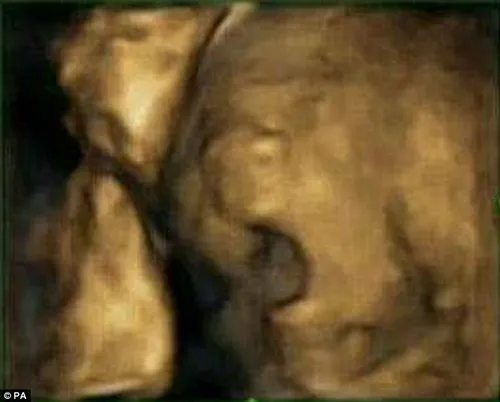

Ongeboren baby's gapen 6 keer per uur in de baarmoeder (foto's)

Onderzoekers aan de Durham Universiteit vroegen zich af of foetussen ook gapen in de baarmoeder. En ja, dat doen ze: gemiddeld 6 keer per uur. Maar ze geeuwen niet omdat ze moe of verveeld zijn. De onderzoekers bestudeerden foetussen van 15 moeders in spe en maakten 4 keer 4d echo's tijdens hun zwangerschap, de laatste op 36 weken. Sommige academici beweren dat de baby's gewoon hun mond openen en sluiten. Maar volgens Dr. een van de onderzoekers, leveren de scans onomstotelijk bewijs dat zij daadwerkelijk gapen. De jongste foetussen geeuwen het meest. Foetussen gapen waarschijnlijk niet omdat ze moe zijn. Dr. Reissland gelooft dat het gapen een teken is van hersenontwikkeling; het ontwikkelt de kaak van de foetus die nodig is om te kunnen eten. Zij denkt dat het gapen in de toekomst een indicator kan zijn om te bepalen of een foetus zich normaal ontwikkelt. Zie hier indrukwekkende foto's en een video. Bekijk er meer.